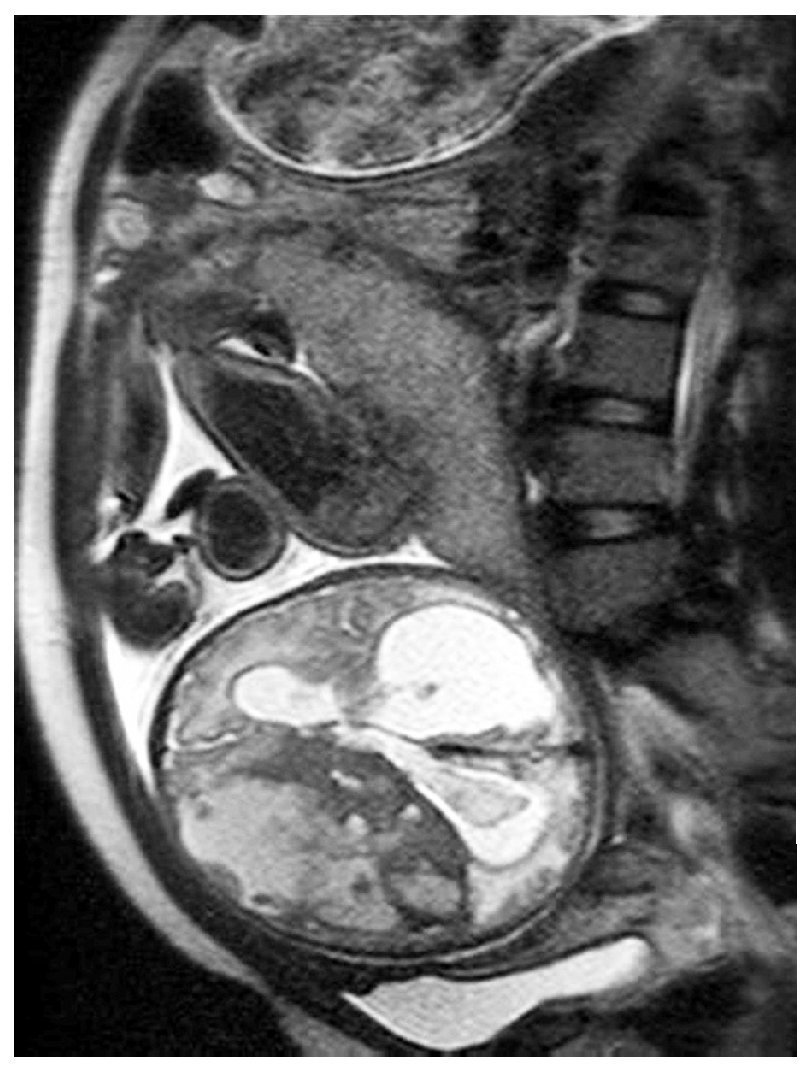

Gestante en el séptimo mes del embarazo. En ecografía de control se detecta hidrocefalia.

Fig. 1.